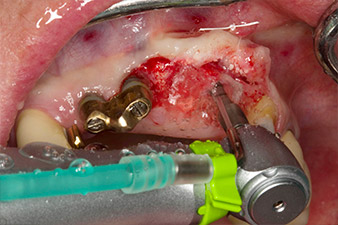

Gewindeschnitt mit dem Winkelstück WS-75 L

Abb. 3: Gewindeschnitt mit dem Winkelstück WS-75 L bei einer Übersetzung von 20:1 (Programm P4). Hilfreich sind hier das hohe Drehmoment des Implantmed, das Hexagon-Spannsystem für sichere Kraftübertragung und die automatische Umkehr der Drehrichtung bei zu hohem Widerstand.

Maschinelles Eindrehen des Implantats

Abb. 4: Maschinelles Eindrehen des Implantats mit dem Winkelstück WS-75 L bei einer Übersetzung von 20:1 (Programm P5).

Um den parodontalen Knochenverlust auszugleichen und ein ästhetisches Ergebnis zu erreichen, wird die Implantation mit gesteuerter Knochenregeneration mit xenogenem Ersatzmaterial und einer Kollagenmembran kombiniert (Abb. 5 und 6).